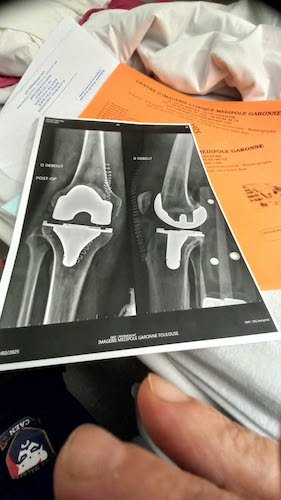

Figurez-vous qu’après Daniel ( viewtopic.php?t=2333 ), j’ai rencontré Miguel qui m’a donné 2 photos de son genou opéré. Une prise AVANT l’opération et l’autre APRÈS.

La photo du genou de Miguel APRÈS.jpg

La photo du genou de Miguel APRÈS.jpg (30.23 Kio) Vu 4138 fois

Miguel a une pêche d’enfer. Il devrait reprendre doucement le vélo en juin et a prévu de nous montrer son dossard en septembre quand il reviendra dans le peloton de la Carrerrasse.